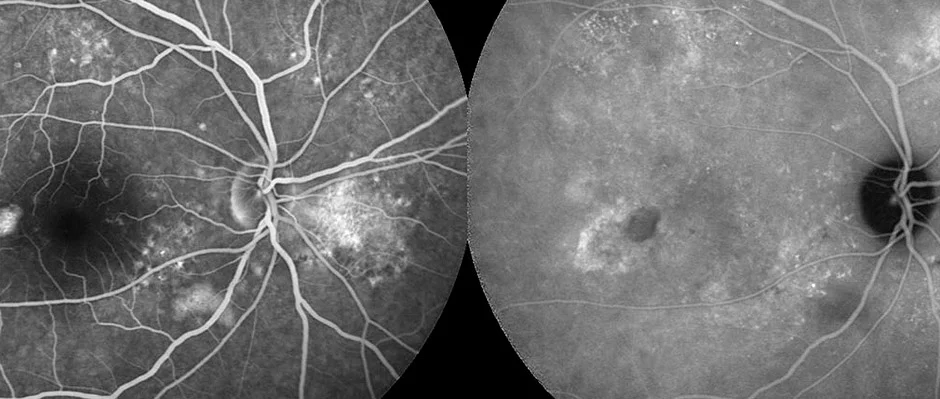

Exame diagnóstico vital na oftalmologia que nos permite visualizar a circulação sanguínea na retina e no coroide.